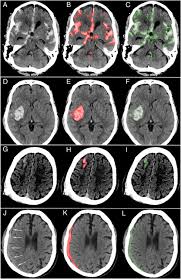

These imaging tests are generally more sensitive to acute bleeds in emergency situations than magnetic resonance imaging (mri). There are several types of brain bleeds, and while they are dangerous, recovery is possible. Symptoms of a brain bleed can include: If it occurs, there is usually a precipitating factor. Justanswer.com has been visited by 100k+ users in the past month Some blood vessels in the brain are more likely to bleed than others. Often, rehabilitation is necessary after recovery from a brain bleed. 3 to 14 days prior 3.

With that said, mris are better able to detect smaller intracranial hemorrhages than ct.12 besides identifying the location of blood in the brain, imaging tests are also able to determine the size of a bleed and whether a blood clothas formed. Sudden tingling, weakness, numbness, or paralysis of the face, arm or leg, particularly on one side of the body. Feb 05, 2016 · occasionally, you won't feel any initial symptoms. Causes and types of bleeding in the brain include: There are several types of brain bleeds, and while they are dangerous, recovery is possible.

Causes and types of bleeding in the brain include: See full list on verywellhealth.com A brain bleed can also cause irritation, a stiff neck, impulsiveness and issues managing your temper. The symptoms of brain hemorrhage are as follows: Some symptoms of brain hemorrhage are common to all stroke warning signs: See full list on verywellhealth.com Symptoms of a brain bleed can include: Based on imaging tests, lab technicians can determine when a subdural hematoma first started, the timing of which is classified into three categories: